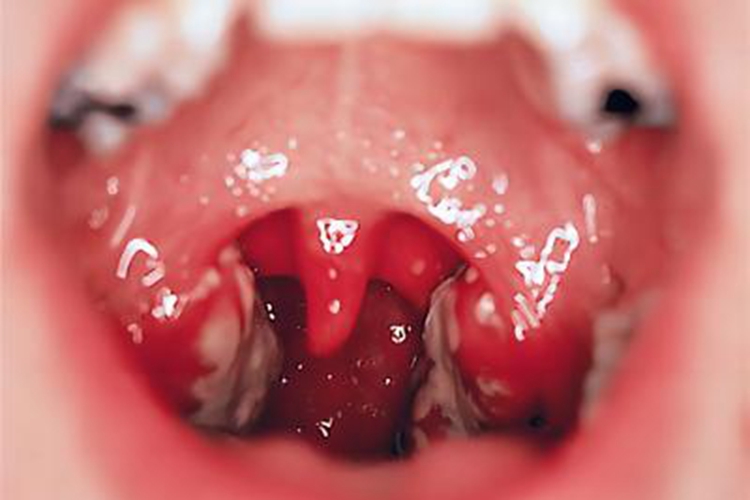

急性隐窝性扁桃体炎患者在临床上可表现为双侧扁桃体红肿明显,突出于隐窝,隐窝口处有很多白色小点样渗出物,且相连形成片状皮损,咽痛症状甚至会放射至耳部。

该症状主要是扁桃体隐窝内存留着某些病原体导致感染引起,乙型溶血性链球菌为主要致病菌。受凉、潮湿、有害气体刺激、上呼吸道有慢性病灶存在等因素均可诱发这种情况出现。其典型症状表现为扁桃体充血、肿大,隐窝口处有黄色点状渗出物。